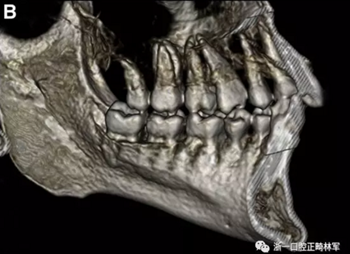

在輸出的3D模型上,使用體內軟件(Anatomage,San Jose,Calif)將下頜骨以最小的間隔從顱骨上分離(圖5)用于保留下頜骨的咬合細節,游離的下頜骨被保存(圖6,A)。同時,將沒有下頜骨的顱骨導出并保存(圖6,B)。

圖5. 在磨牙區域清晰顯示間隔并保留咬合細節的二維切片。

圖6. A,從整個3D模型上修剪的下頜骨; B,修剪的顱骨。